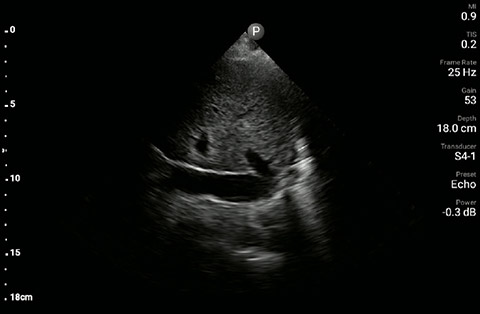

The patient had reduced LV systolic function without new or severe valvular pathology, a dilated, non-collapsing IVC, and diffuse B lines (left greater than right) on lung ultrasound imaging.

Apical 4-chamber

Parasternal long-axis